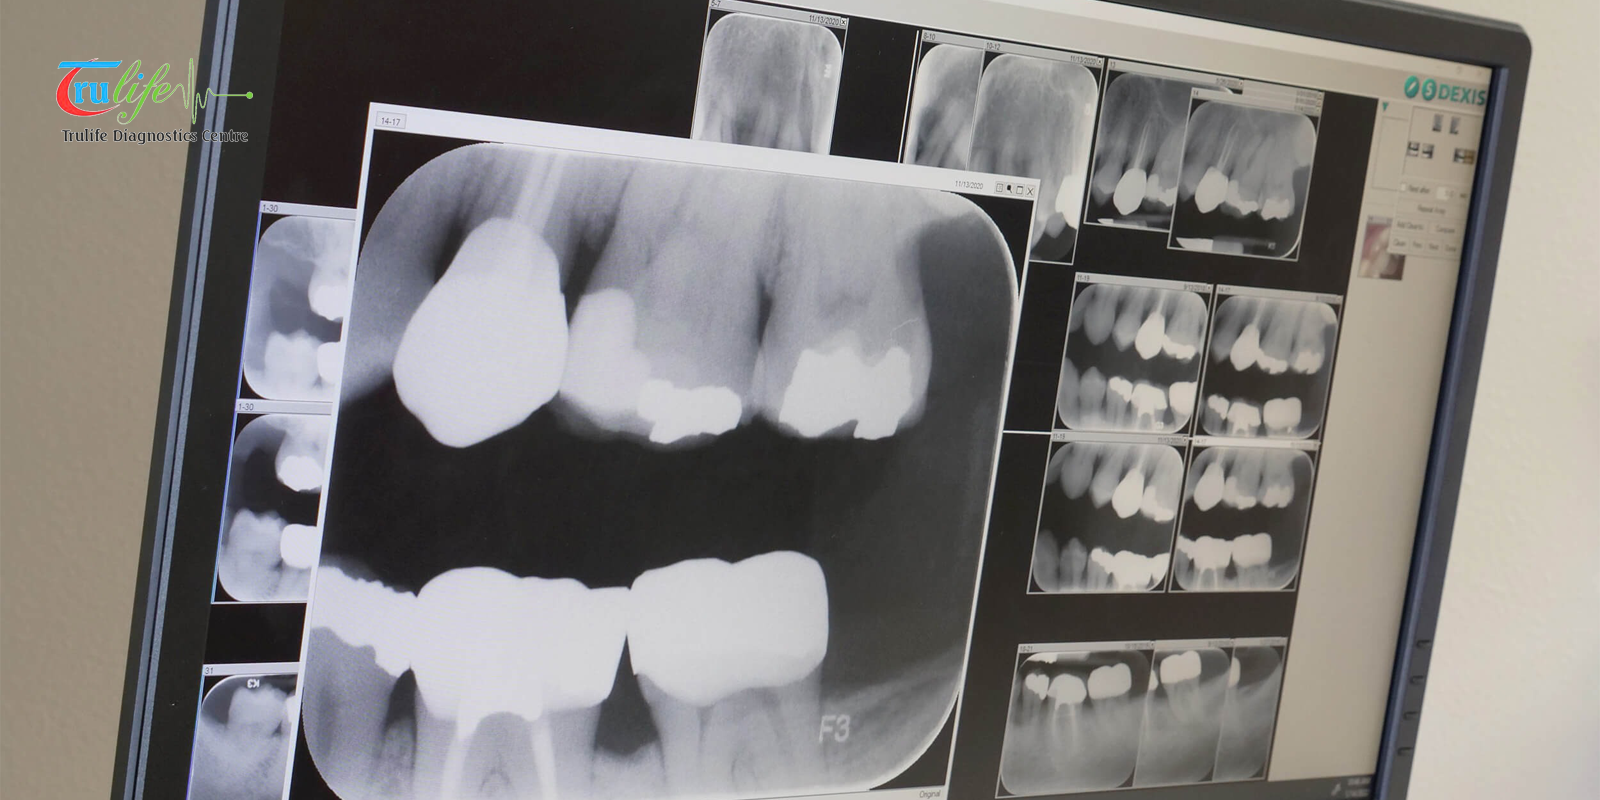

In modern healthcare, early diagnosis saves lives—and one of the most vital tools enabling this is the Digital X Ray Narsingi service offered by TruLife Diagnostics Center. Digital radiography has […]